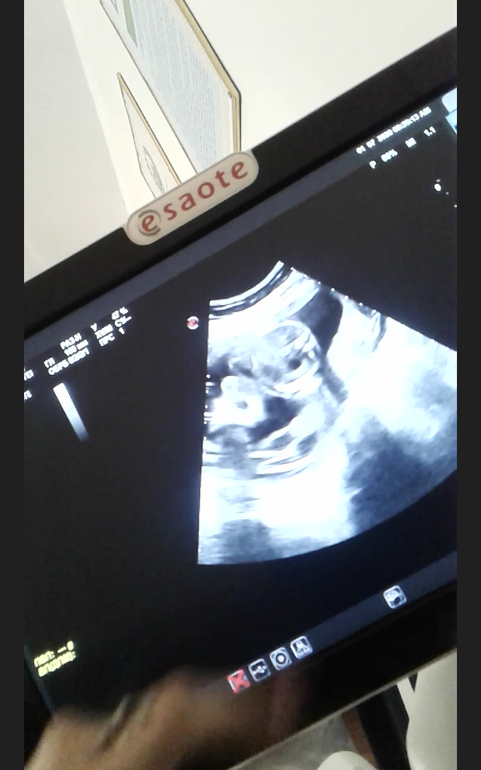

19 неделя и 2 скрининг.

Всё о нашей беременностиВот и прошли мы 2 скрининг , тьфу тьфу все хорошо. Сегодня, наконец подтвердили наш пол. Мужичок. ))) Ну и фоточки на память, какие мы были и какие мы сейчас. Все кто ждет своих пузожителей , пусть уууу всееех всеее получится.. На всех ждунов, заразнейший чих , мальчуковый : ААААПЧХИИИИИ...... Пусть все будет забеременительно.....

А это мы сейчас :